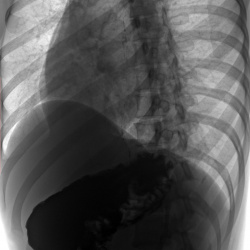

Здравствуйте! Помогите, пожалуйста с диагностикой! Здесь есть каскадный желудок? В заключении написано гастроптоз 3 степени и хронический гастрит. У меня демпингоподобный синдром и гастрокардиальный (головокружение после сладкого, бывает после основного приема пищи, падает давление после еды). Я уже измучилась. У эндокринолога, кардиолога, невролога консультировалась, все говорят это гастроентерологическое. Если надо есть снимки мрт и кт органов брюшной полости. Буду признательна

Не вижу признаков каскадного желудка, не п сал бы гастроптоз, демпинг синдром является осложнением оперированного желудка (нет р-признаков резекции)